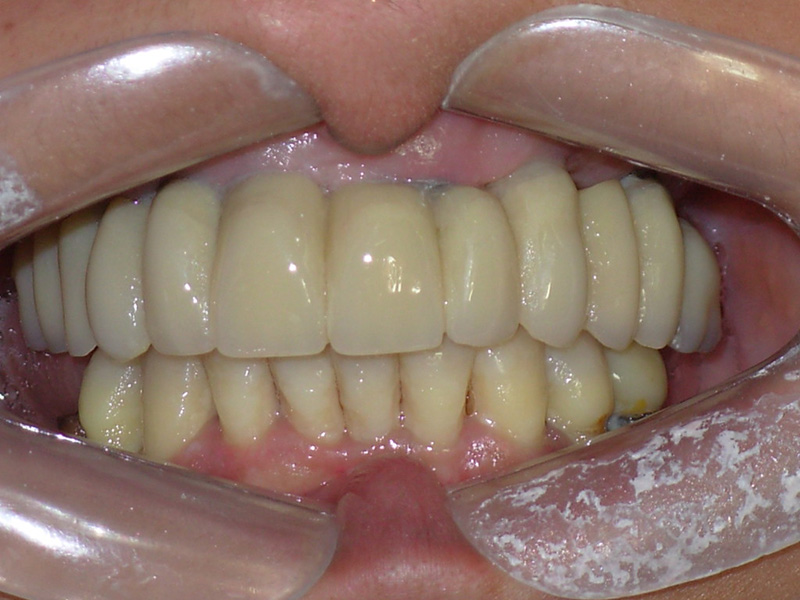

Na Clínica Pontes Odontologia, somos referência em implantes dentários em Fortaleza, oferecendo tratamentos de alta qualidade e tecnologia de ponta. Os implantes dentários são estruturas de titânio posicionadas cirurgicamente no osso maxilar ou mandibular para substituir as raízes dos dentes ausentes. Essa técnica permite a fixação de próteses personalizadas, restaurando a função mastigatória, a estética e a autoestima dos nossos pacientes.

Utilizamos a tecnologia CAD CAM, um sistema avançado que possibilita a confecção precisa das próteses dentárias diretamente sobre os implantes. Esse método inovador garante um ajuste perfeito, um resultado estético superior e proporciona muito mais conforto e durabilidade. Com o CAD CAM, nossos pacientes contam com um processo mais rápido e previsível para alcançar o sorriso desejado.